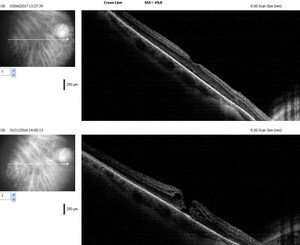

El diagnóstico se realiza realizando un examen de fondo de ojos y se confirma con la tomografía de coherencia óptica (OCT) que determina la extensión del agujero, lo cual sirve para ver el pronóstico (mejor cuando es < 400 micras). También sirve para distinguir un agujero macular lamelar de una agujero macular completo. Además confirma el cierre del agujero en el postoperatorio.

Figura 4. Imagen en la OCT: agujero macular inferior y agujero cerrado post cirugía.